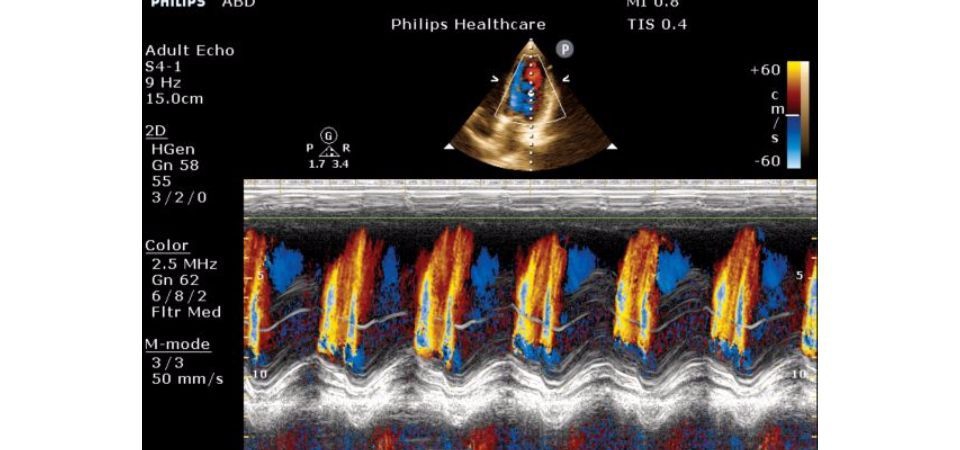

• Функция AutoSCAN: Динамическая оптимизация качества изображений во время сканирования позволяет получать результаты высокого качества. Криволинейные области интереса и автоматическое определение лица плода обеспечивают 30 инструментов редактирования, специально разработанных для повышения производительности в акушерских исследованиях. Функция стресс-эхокардиографии стандартизирует просмотр стресс-исследований сердца.

Цветной M-режим:

M-режим:

Да

• Стресс-эхокардиография - Да

• Поддержка тканевого доплера (TDI) - Да

TDI, iScan Color and Doppler, High Q, Anatomical Mmode, Stress